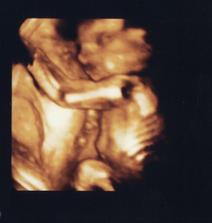

25.11. Na kontrole vše v pořádku. U ultrazvuku byl i budoucí tatínek a malý se náležitě předvedl. Vypadá to, že bude dělat Break dance 🙂 Má všechno, co mít má. Pan doktor nám sám od sebe ukázal i 3D UZ a vytiskl fotečku. Manžel sám od sebe jel nakoupit dětské oblečení a užíval si to málem více než já. Je krásné vidět, jak se na prcka těší. A viděli jsme camfrlika (výraz gynekologa) mezi nožkami 🙂